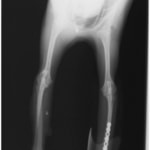

ペルシャ猫 11ヶ月齢 雄

他院にて左大腿骨遠位の成長板骨折(salter-harrisⅠ型)が認められており、治療相談を目的として来院。当院にて、キルシュナーワイヤーを用いたピンニングにより骨折部位の整復を行いました。術後の経過は良好で、現在も経過観察中です。

術後レントゲン